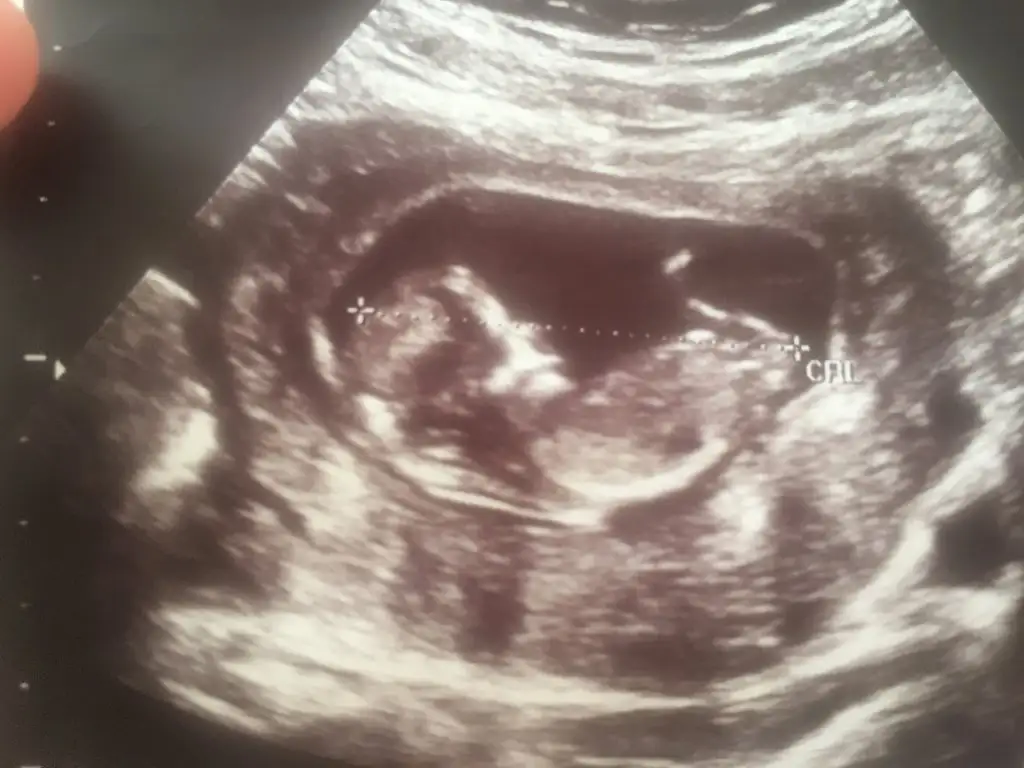

Bana da bakarmısın 11+4 haftalık karından bakıldı

Eklentiler

• 554A11E3-2185-45AE-906B-C2E8711D7691.webp

26,8 KB · Görüntüleme: 150